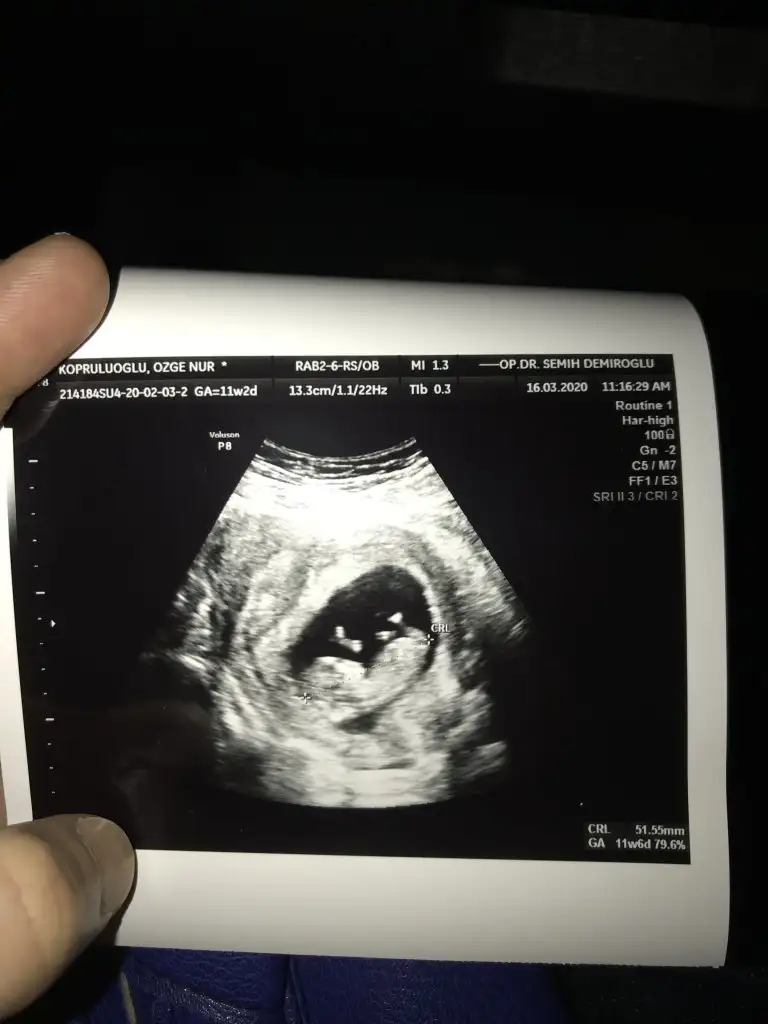

benimkine de bakar mısınız

merhaba 12 haftalık hamileyim bende bugün ikili tarama yaptırdım cinsiyet tahmininizi alabilir miyim :)

Eklentiler

• E5C92BC7-7E7F-4A45-8611-64A3B20844EA.webp

E5C92BC7-7E7F-4A45-8611-64A3B20844EA.webp

40,6 KB · Görüntüleme: 51

• A6DDA7B7-A56E-42F6-8D66-E4AAC8182DA4.webp

A6DDA7B7-A56E-42F6-8D66-E4AAC8182DA4.webp

26,7 KB · Görüntüleme: 46